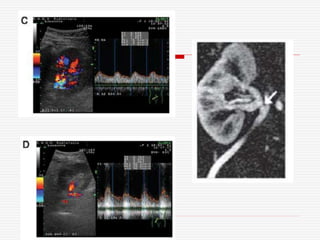

• 61.

35 year-old :Doppler ultrasound showing parvus-tardus pattern with collapsed resistance index Normal right kidney